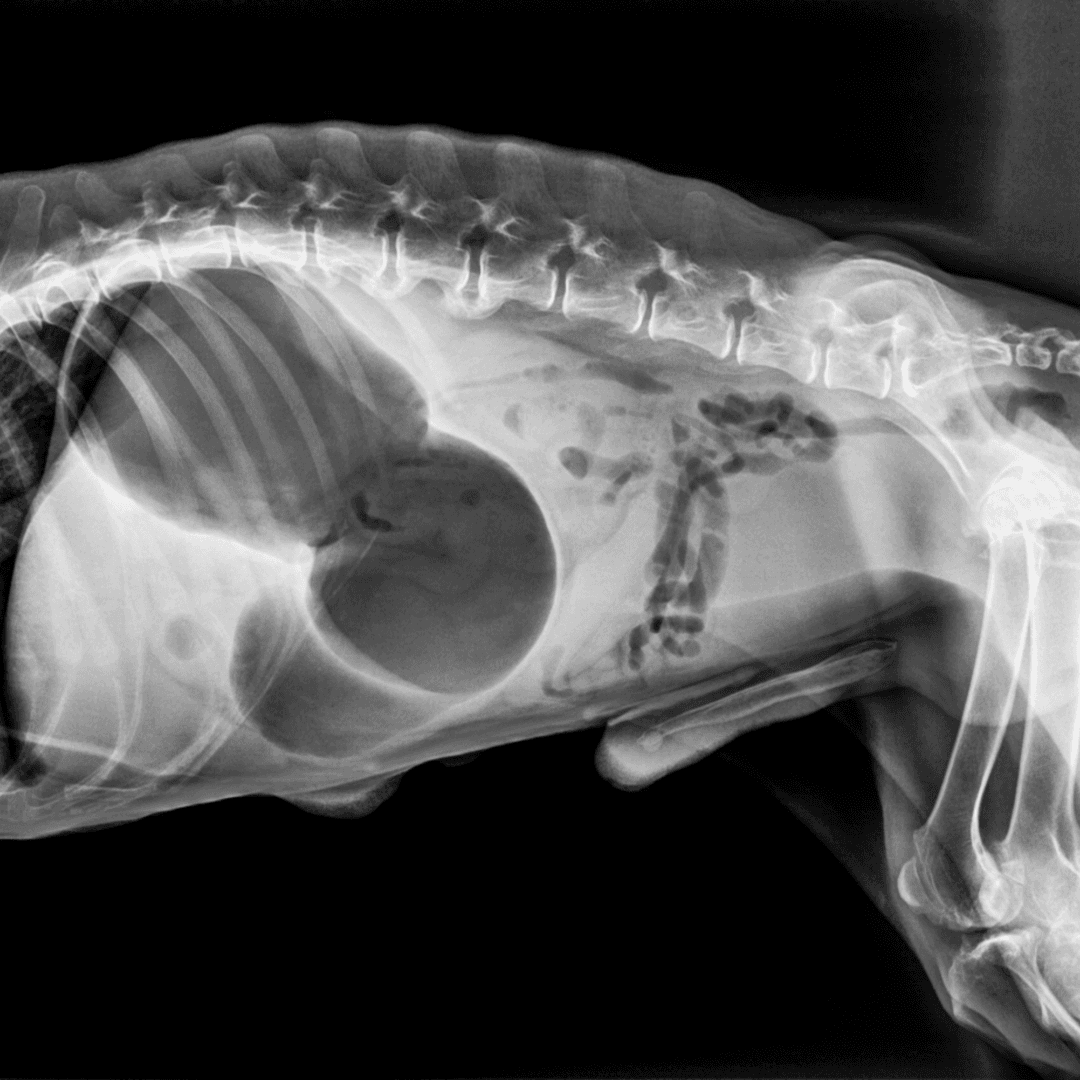

Feline Urethral Obstruction

Feline urethral obstruction (UO) is a life-threatening and painful condition, affecting up to 10% of the feline population. Appropriate management can result in a favorable prognosis. This article discusses approaches to the diagnosis and treatment of urethral obstruction in cats, with an emphasis on clinical decision-making and effective intervention strategies.